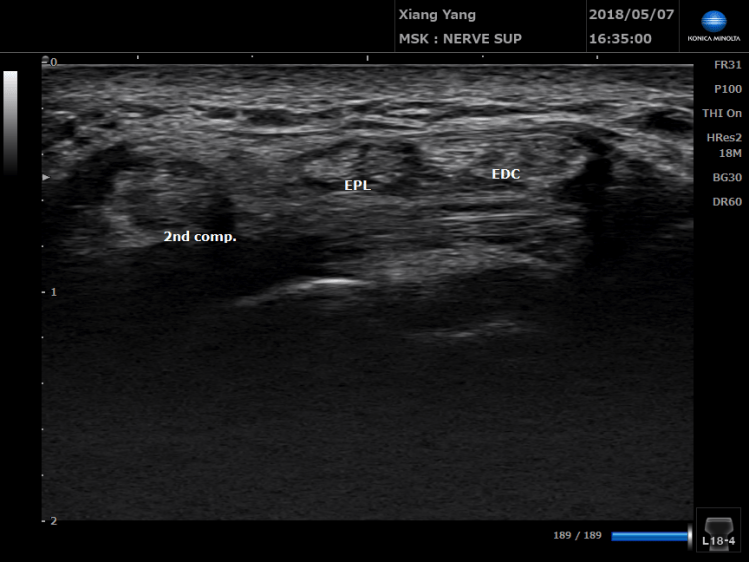

常被誤診為媽媽手的隔間症候群(Intersection syndrome)。

26歲男性,昨天玩傳說對決(DC超人),因為該角色操作需要反覆的手腕伸直和大拇指的動作,隔天手腕無法做往背側伸展的動作.

格肩症候群痛的位置比媽媽手還要在中間一點,除了打針與物理治療以外,使用貼紮減少肌腱的用力。可以更快回到正常工作。